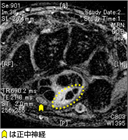

1. 超音波検査の有用性について国内でも一定の見解が得られたため、米国のガイドラインの内容を反映させた(Cartwright MS et al. Muscle Nerve. 2012 Aug;46(2):287-93.)。

1. 確定診断と鑑別診断のために手根管の超音波検査を行う(推奨度2)